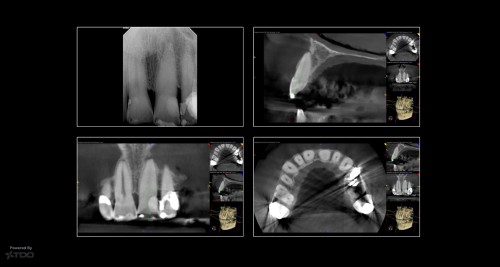

Pt presented with persistent sinus tract on B

Pt presented with persistent sinus tract on B. RCT’s done by another endodontist in town. […]